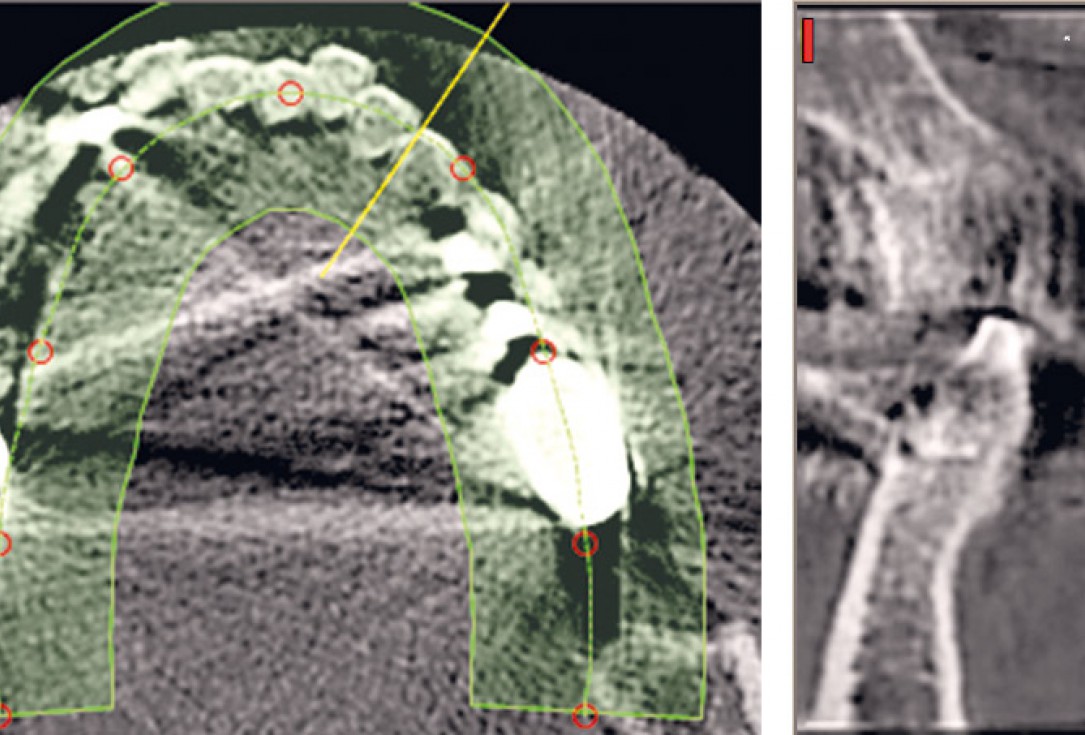

21 / 22 - CBCT image of the first quadrant one year after augmentation

22 / 22 - Optimal implant position and bone volume stability one year after augmentation